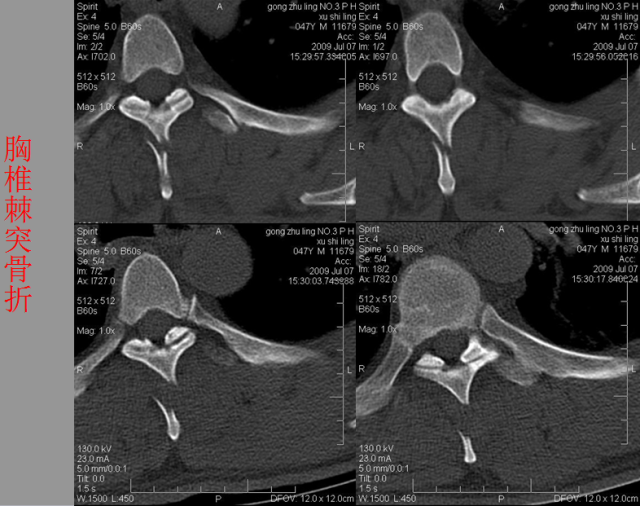

骨折篇

定义:骨折{Fracture}是指骨的完整性和连续性的折裂或粉碎。包括创伤性骨折、疲劳性骨折和病例理性骨折。 临床上以创伤性骨折*常见。